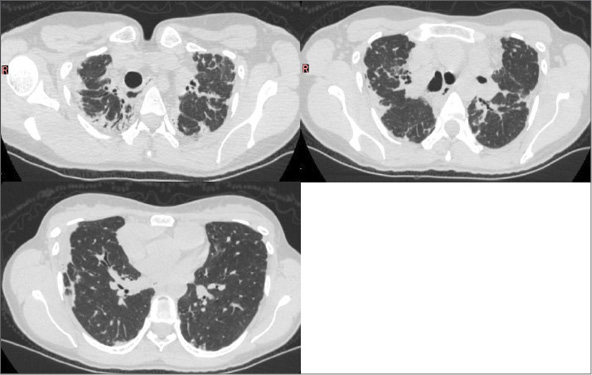

Mujer de 39 años con exposición a humo de biomasa durante 3 años, sin antecedentes de tabaquismo, nuemotóxicos, tuberculosis, ni enfermedades autoinmunes. Presentó dolor torácico, disnea y pérdida de peso de 4 años de evolución. Fue inicialmente diagnosticada con secuelas de tuberculosis. (Figura 5) Una nueva TC evidenció opacidades fibro-retráctiles pleuropulmonares, disminución volumétrica de lóbulos superiores, distorsión arquitectural con progresión hacia lóbulos inferiores y marcada depresión en horquilla supraesternal. (Figura 6) Patrón restrictivo muy severo (CVF 23%), difusión de monóxido de carbono (DLCO), descenso severo 25%. Biopsia pleural, pericárdica y pulmonar mostraron: neumonitis intersticial-septal con predominio de fibrosis, sin patrón de neumonía intersticial usual, ni granulomas ni microorganismos; además pleuritis y pericarditis crónicas inespecíficas.

Caso 2. TC de tórax inicial. Engrosamientos pleurales apicales, disminución volumétrica de lóbulos superiores, consolidaciones pulmonares fibro-retráctiles, con distorsión de arquitectura pulmonar y extensión a lóbulos inferiores. Marcada depresión en la horquilla supraesternal.

Caso 2. TC de Tórax en evolución. Progresión del compromiso fibro-retráctil del parénquima pulmonar, a predominio de lóbulos superiores.